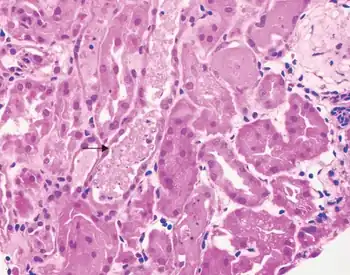

| Acute tubular necrosis-Necrotic and sloughed off tubule epithelial cells filling tubular lumens | |

Histopathology: Toxic ATN is characterized by proximal tubular epithelium necrosis (no nuclei, intense eosinophilic homogeneous cytoplasm, but preserved shape) due to a toxic substance (poisons, organic solvents, drugs, heavy metals). Necrotic cells fall into the tubule lumen, obturating it, and determining acute kidney failure. Basement membrane is intact, so the tubular epithelium regeneration is possible. Glomeruli are not affected.[2]

Acute tubular necrosis is classified as a "renal" (i.e. not pre-renal or post-renal) cause of acute kidney injury. Diagnosis is made by a FENa (fractional excretion of sodium) > 3% and presence of muddy casts (a type of granular cast) in urinalysis. On histopathology, there is usually tubulorrhexis, that is, localized necrosis of the epithelial lining in renal tubules, with focal rupture or loss of basement membrane.[7] Proximal tubule cells can shed with variable viability and not be purely "necrotic".[8][9][10][11][12]